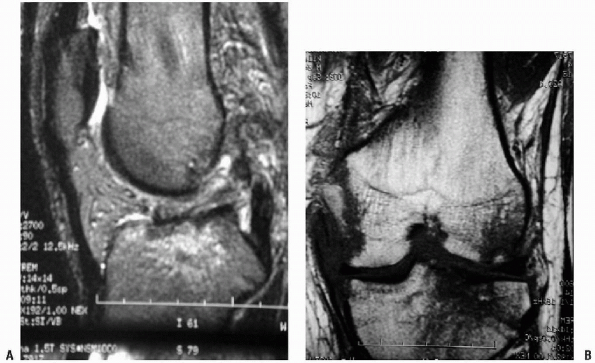

and scheduled for an MRI. The MRI revealed the suspected ACL, LCL, PLC,

and PCL disruptions, as well as bimeniscal capsular disruptions (Fig. 10-4).

Figure 10-4 Sagittal (A) and coronal (B) MRIs of an ACL/PCL/PLC injured knee.